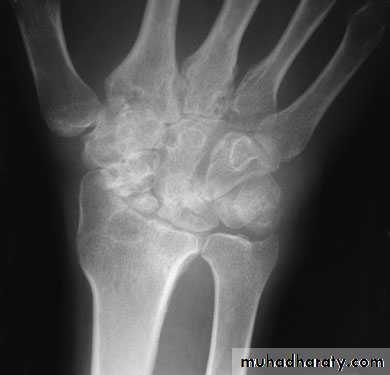

COMMINUTED INTRA-ARTICULARFRACTURES IN YOUNG ADULTS

In the young adult, a comminuted intra-articular fractureis a high energy injury. A poor outcome will result unless intra-articular congruity, fracture alignment and length are restored and movements started as soon as possible. For these patients a much higher standard must be set than would be accepted for the typical osteoporotic fracture. In addition to the usual posteroanterior and lateral x-rays, oblique views and often CT scans are useful to show the fragment alignment. The simplest option is a manipulation and cast. If the anatomy is not restored, then an open reduction may be necessary. The medial complex must be anatomically reduced, which may require open reduction through dorsal and palmar approaches and a combination of wires, plates, screws and bone grafts.